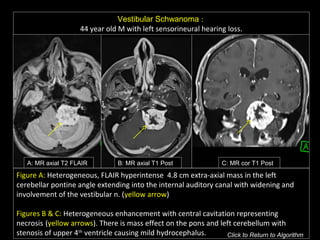

Vestibular Schwanoma :

44 year old M with left sensorineural hearing loss.

A: MR axial T2 FLAIR B: MR axial T1 Post C: MR cor T1 Post

Figure A: Heterogeneous, FLAIR hyperintense 4.8 cm extra-axial mass in the left

cerebellar pontine angle extending into the internal auditory canal with widening and

involvement of the vestibular n. (yellow arrow)

Figures B & C: Heterogeneous enhancement with central cavitation representing

necrosis (yellow arrows). There is mass effect on the pons and left cerebellum with

stenosis of upper 4th

ventricle causing mild hydrocephalus. Click to Return to Algorithm

Vestibular Schwanoma : 44year old M with left sensorineural hearing loss. A: MR axial T2 FLAIR B: MR axial T1 Post C: MR cor T1 Post Figure A: Heterogeneous, FLAIR hyperintense 4.8 cm extra-axial mass in the left cerebellar pontine angle extending into the internal auditory canal with widening and involvement of the vestibular n. (yellow arrow) Figures B & C: Heterogeneous enhancement with central cavitation representing necrosis (yellow arrows). There is mass effect on the pons and left cerebellum with stenosis of upper 4th ventricle causing mild hydrocephalus. Click to Return to Algorithm